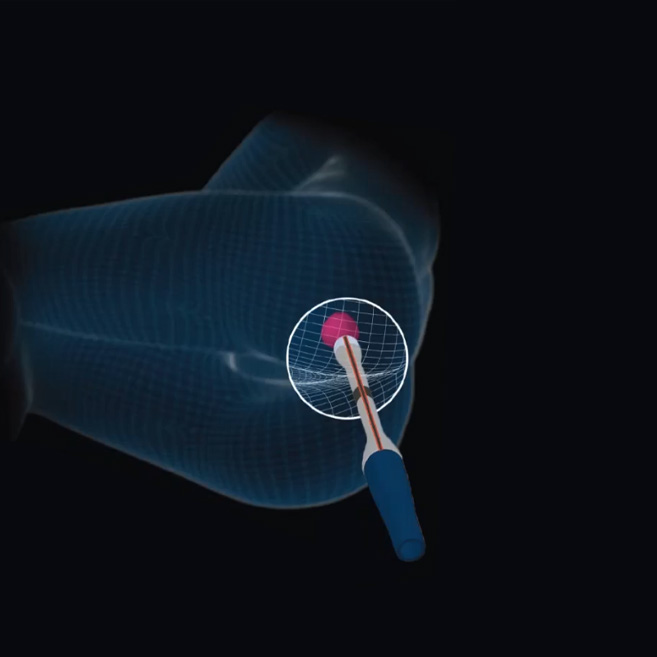

Transrectal

Procedure

KOELIS® 3D ultrasound end-fire probe and accessories enable optimal visualization and targeted interventions via transrectal access.